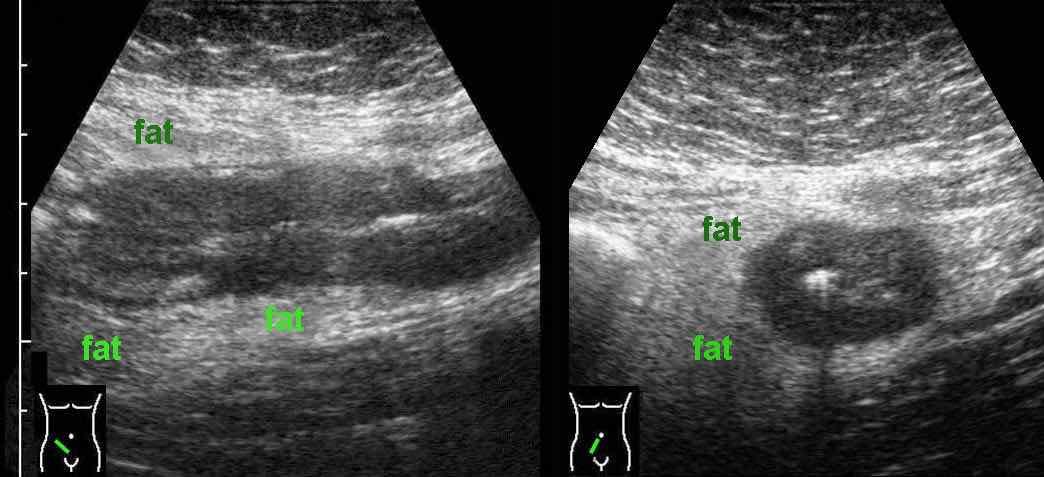

Ở những bệnh nhân có bệnh Crohn hoạt động rõ ràng, cấu trúc siêu âm bình thường của thành ruột có thể bị mất lan tỏa.

Lưu ý mô mỡ tăng âm (fat) xung quanh hồi tràng, đại diện cho mạc treo và mạc nối đang viêm, đang cố gắng bao bọc lại vị trí thủng sắp xảy ra.

Trong những trường hợp như thế này, hình thái thay đổi và lòng ruột hẹp lại có thể bắt chước hình ảnh ác tính.